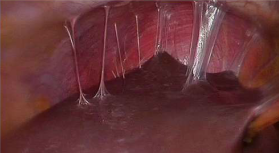

A patient comes in with pelvic pain, fever, mucopurulent discharge, elevated ESR, elevated CRP. She has a history of GC/chlamydia cervicitis. Laparoscopy is shown below What is your diagnosis?

Note Fitz-Hugh-Curtis adhesions over the liver, typical of PID.